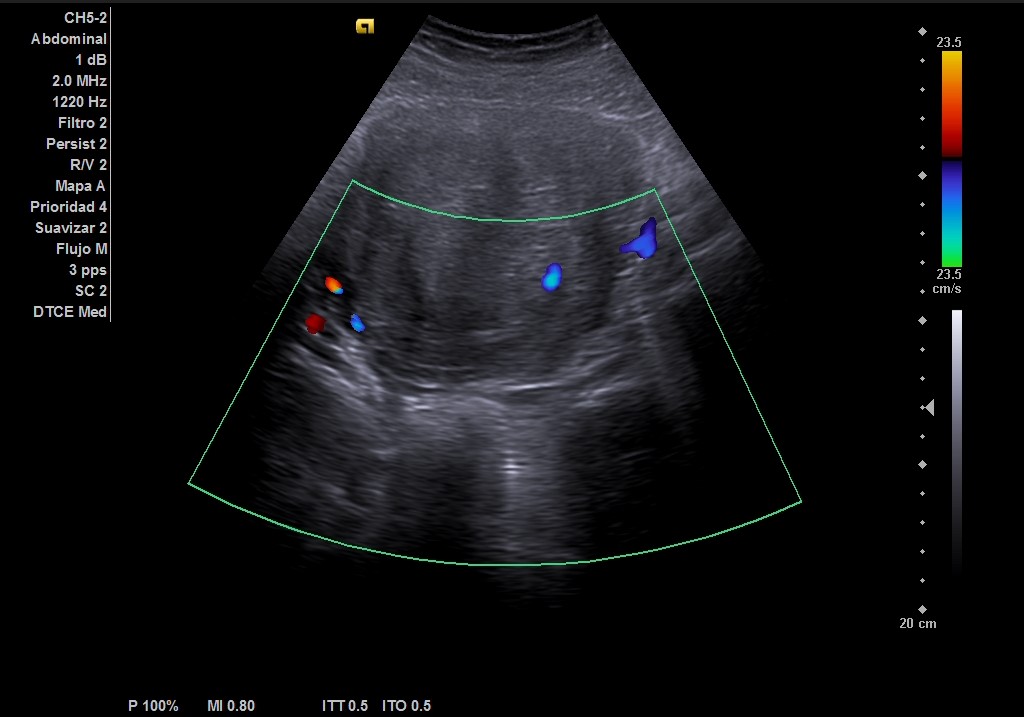

Ecografía abdominal: masa heterogénea de 10 x 10 cm dependiente de útero con vascularización periférica. No se observa la vejiga al estar repleccionada y desplazada por dicha masa. Se vuelve a hacer ecografía con vejiga llena y se observa cómo deforma la pared por efecto masa. Vejiga sin litiasis en su interior, no globo vesical.